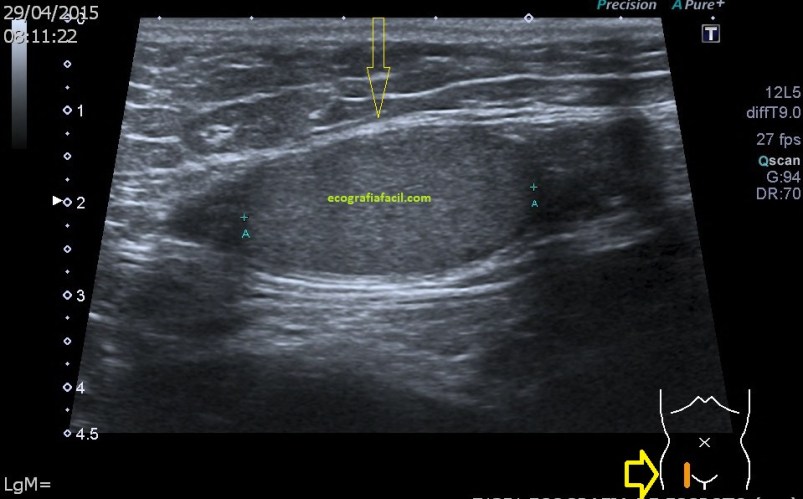

La mayoría de las exploraciones están dentro de la normalidad, este aspecto:

En algunas ocasiones podemos encontrarnos esto:

Compara la imagen 1 y la 2, grábala en tu memoria fotográfica. Ambas son unas imágenes en corte longitudinal del teste derecho de dos pacientes distintos.